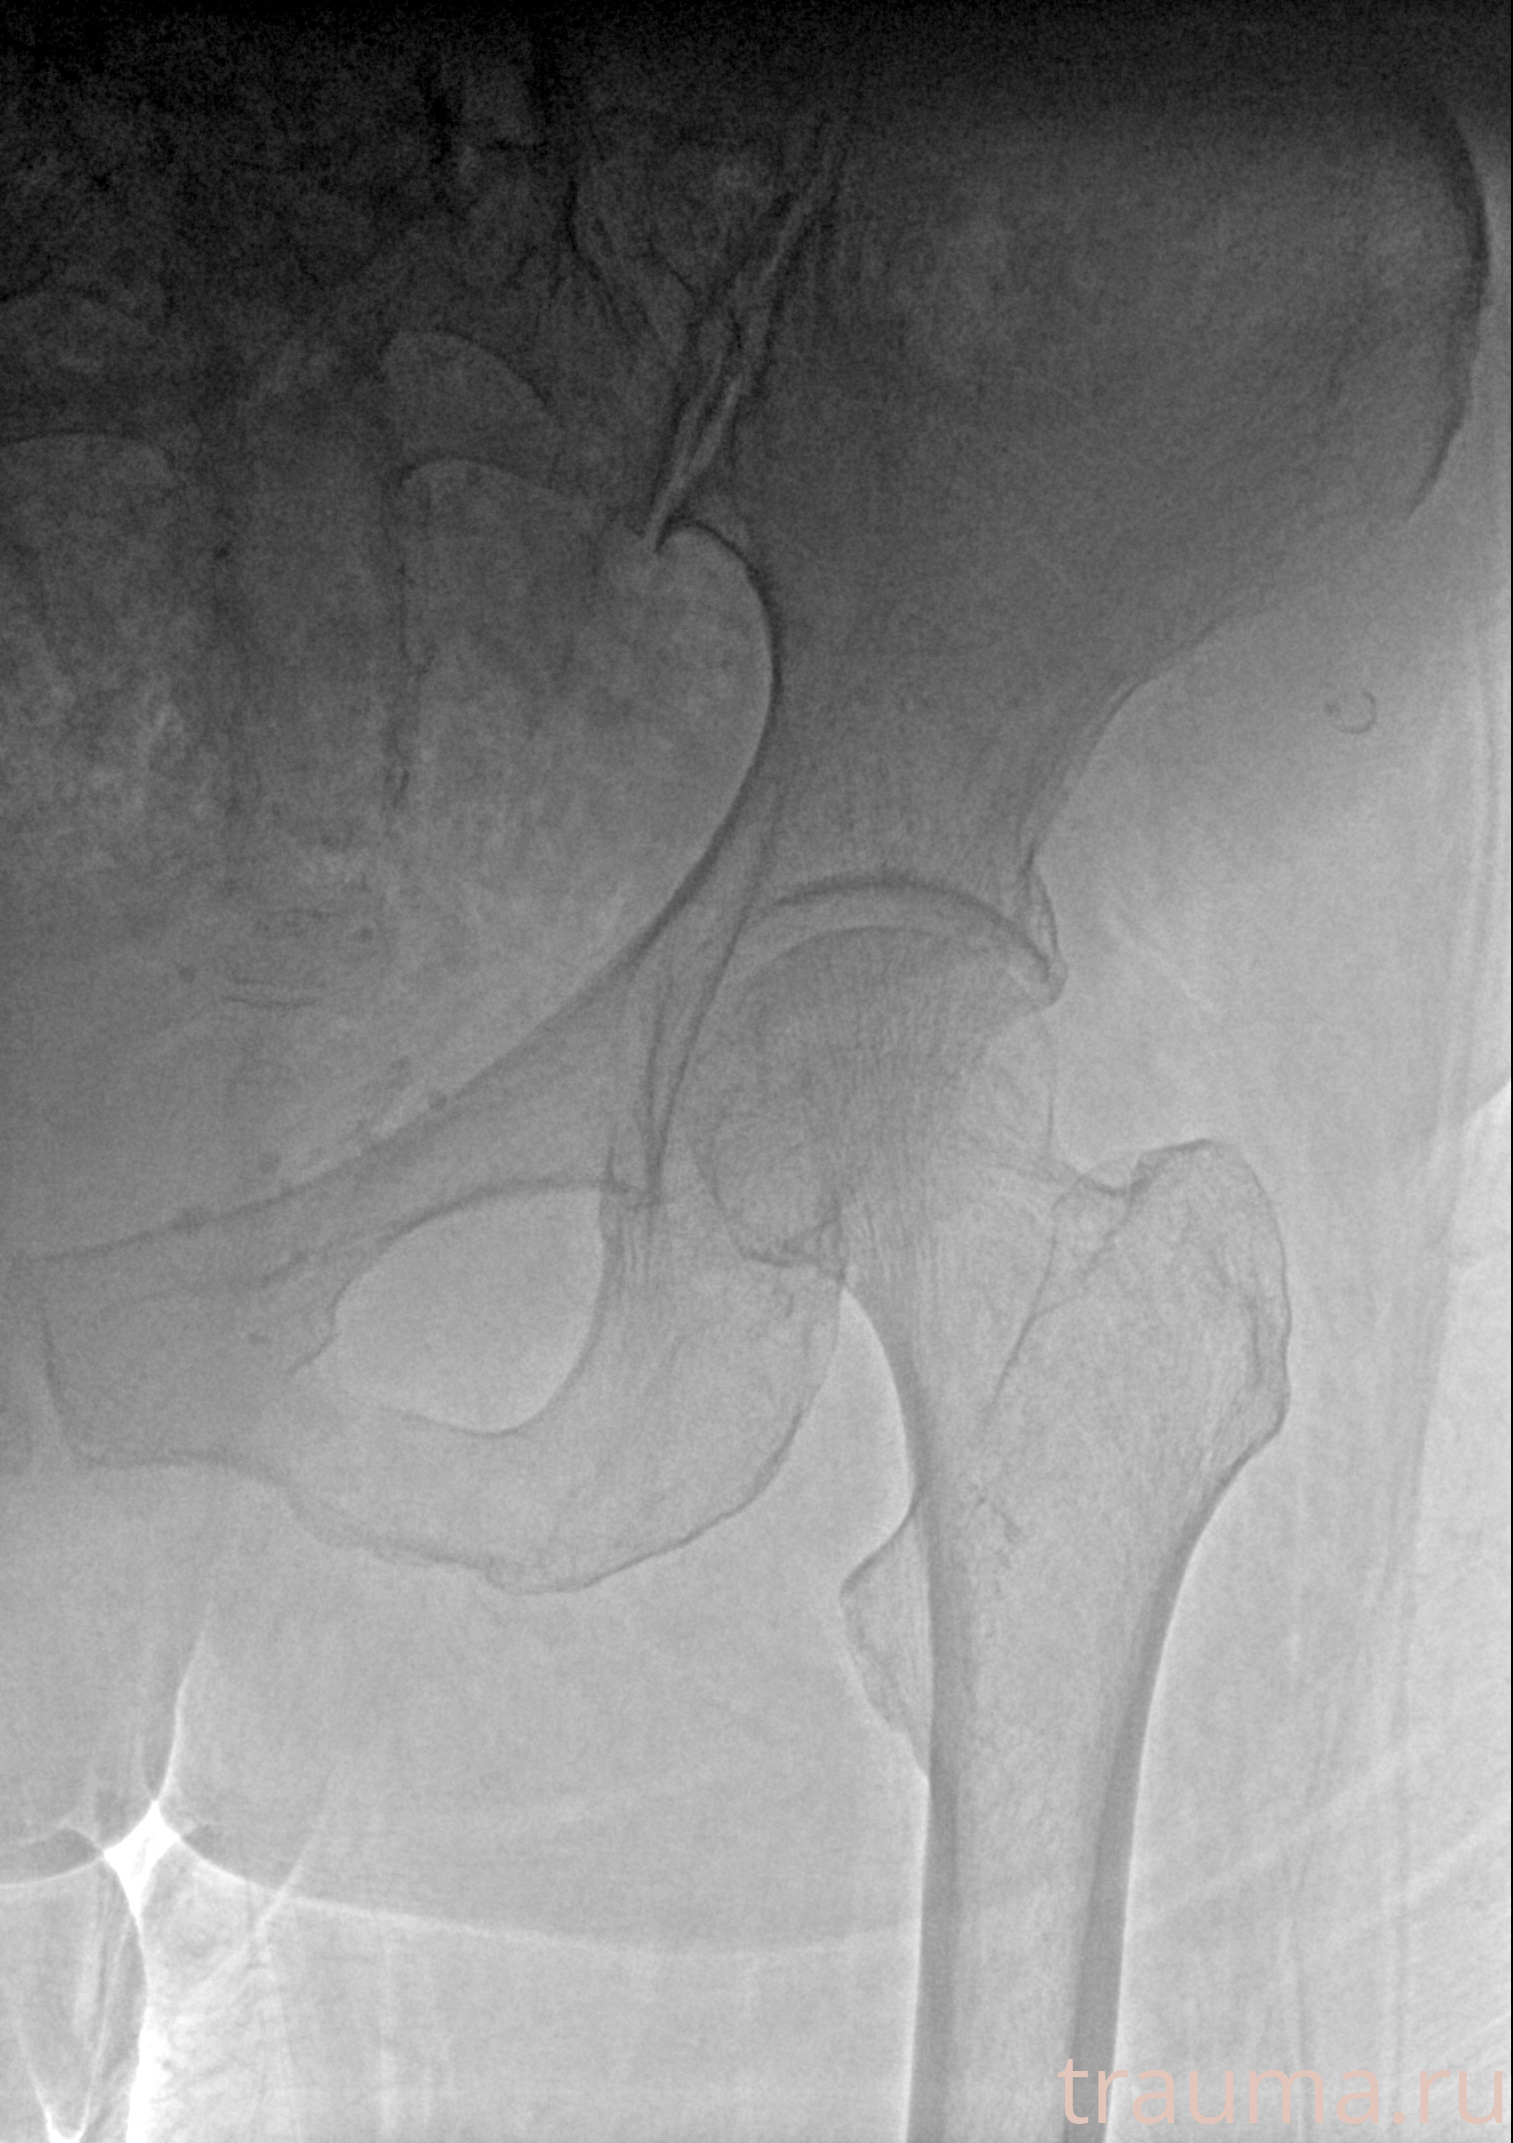

Рентген на дому: по вашему адресу приезжает врач-рентгенолог, травматолог-ортопед с мобильным рентгеновским аппаратом, проводит диагностику травмы или заболевания, делает необходимые рентгенограммы, дает рекомендации по дальнейшему лечению. Получить качественные снимки в домашних условиях возможно благодаря уникальной методике, разработанной МосРентген Центром для института  Склифосовского